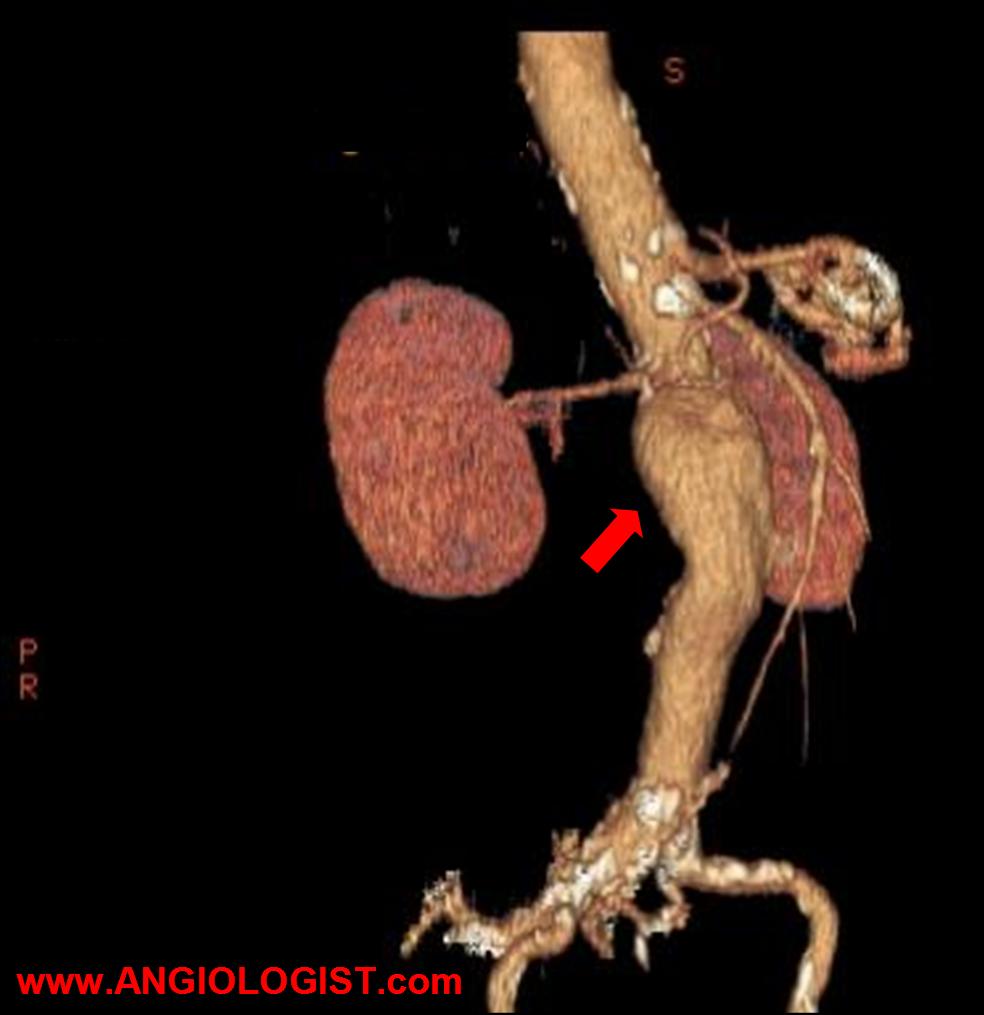

In the past, the only options for abdominal aortic aneurysm treatment were surveillance or surgery. Today endovascular repair of aortic aneurysms is usually the treatment of choice. Of course, choosing between surveillance, endovascular and surgical repair can be hard. It requires an understanding of the natural history of AAA as well as the short and long-term outcomes of the various treatment options.

Typically, an abdominal aortic aneurysm is treated if the size is over 5-5.5 cm. Other reasons to treat are if the rate of progression is high, or if there are other high-risk factors. A high progression rate is more than 0.7 cm/6 months. Another reason to intervene are complications. For example, embolization, compression of adjacent structures and pain.